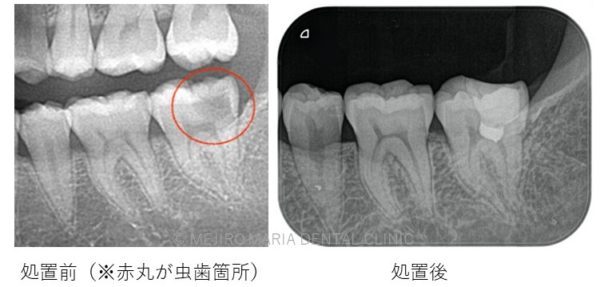

C1 ~ C2について

C2まで進行すると、甘味痛、咬合痛、冷水痛などの不快症状が確認できることがあります。

しかし、無症状で虫歯が進行する場合もあります。虫歯箇所に水や食べ物が侵入しづらい場合は知らないうちに虫歯が進行することもあるためです。

処置が必要になった場合は、コンポジットレジン修復、または歯冠修復(被せもの)で対応します。歯冠修復は一度型取りを行い、装着と調整を行わなければいけませんが、しっかりとした歯冠形態が復元されるため将来的な虫歯や歯周病のリスクを低減することができます。

セラミック素材のものは口腔内の環境に配慮した装着を行うことで虫歯のリスクを更に低減することが可能です。